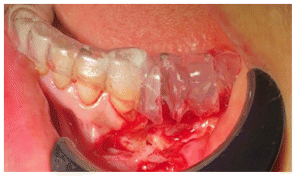

Due to the size of the lesion a mandibular titanium rod was placed to preserve the the lower portion of the mandible and part of the ascending ramus and condyle of the mandible (Figures 6,7,8) In the panoramic rx, the placement of the titanium rod can be seen to fix the ascending ramus with the condyle and the right side of the mandible with the resection to the level of the left lower canine (Figure 9).

Subsequently, a Walter Lorenz Titanium mesh (Figure 10,11) was used to contain the autologous bone that was obtained from the anterior iliac crest mixed with BMP2 morphogenetic protein (Cowell PLUS BMP), as well as Alogen bone mixed with growth factors and membranes with the Chuckron technique (Figure 12, 13,14)